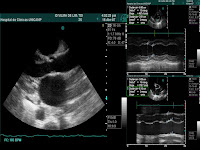

O assunto atual é ecocardiograma 3D.

Uma visão tridimensional, mesmo em tempo real, interessa mais na avaliação pré intervenção cirúrgica. Tumores, por exemplo, precisam de uma definição espacial precisa para orientar o cirurgião.

O que interessa na clínica cardiológica é a avaliação funcional, quando voamos para definição espacial somos facilmente superados pela ressonância e Tomografia.